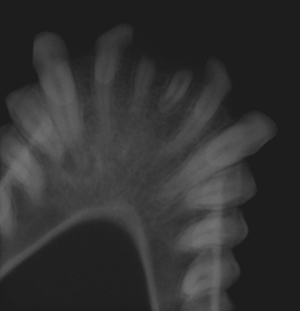

Here is the digital intraoral radiograph of the patient. (R)

What radiological pathology can you see on this intraoral ventro-dorsal view?

Similar to humans, primates have 2 incisors in each quadrant, one less than carnivores. The root

remnants of both central incisors are present.

There is a large area of bone loss associated with the apices of the left mandibular canine tooth

(33) and premolar (34). On intra-oral examination, tooth (33) was discoloured compared to tooth 34

and pulp exposure could also be detected on tooth 33 using a shepherd’s hook explorer. Tooth

discolouration is a sign of loss of vitality of the tooth. The pulp infection/inflammation spread

through the apex to the adjacent periapical bone which resulted in the recruitment of bone

resorbing osteoclasts. Pulpitis/pulp necrosis may give rise to periapical granuloma/cyst/abscesses,

all of which will give a similar radiological image and can only be diagnosed on histological

examination.